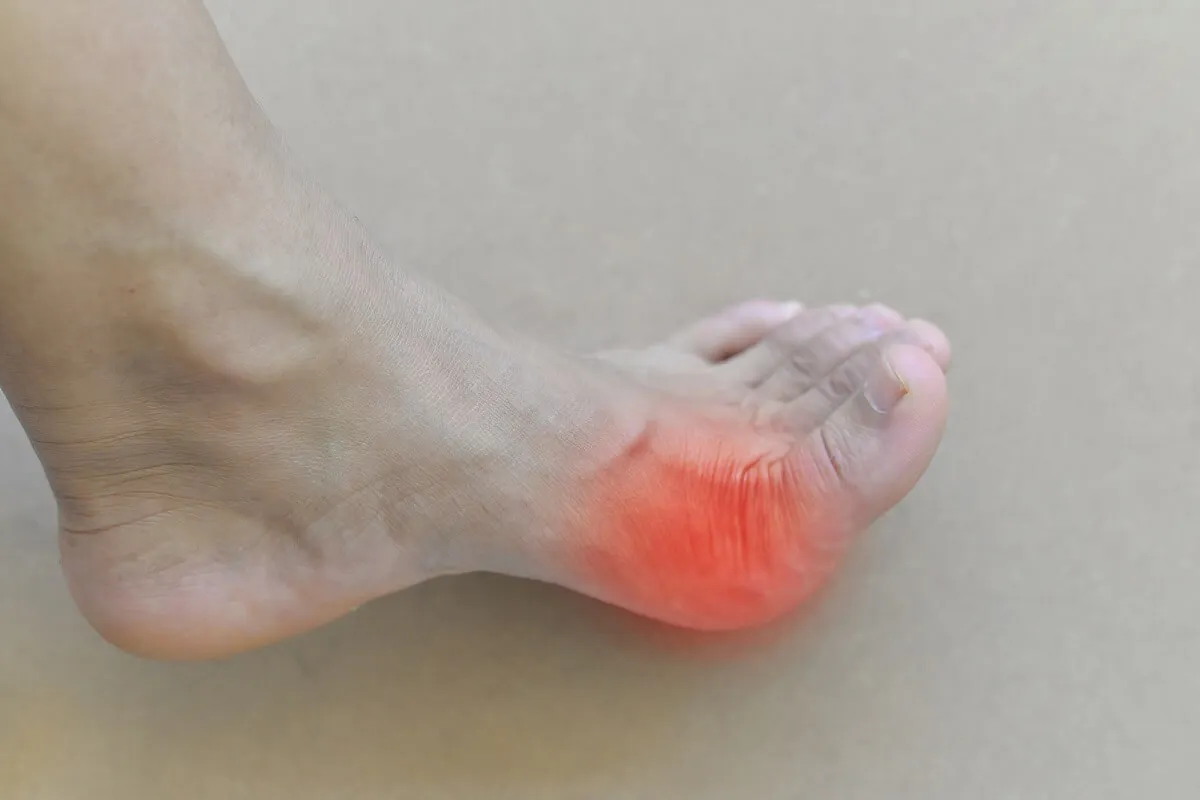

La acumulación de cristales de ácido úrico en las articulaciones provoca dolor e inflamación. Por ello, quizá lo último que desee una persona afectada es adoptar una rutina de ejercicio físico. De hecho, cuando se producen los brotes, la recomendación general es descansar y evitar cualquier sobreesfuerzo.

Sin embargo, una vez mejoran los síntomas (con el tratamiento recetado por el médico), hacer ejercicio regular puede tener un impacto positivo. Los movimientos no solo disminuyen la rigidez articular, sino que contribuyen a bajar de peso y a controlar otros factores que suponen complicaciones en la hiperuricemia.